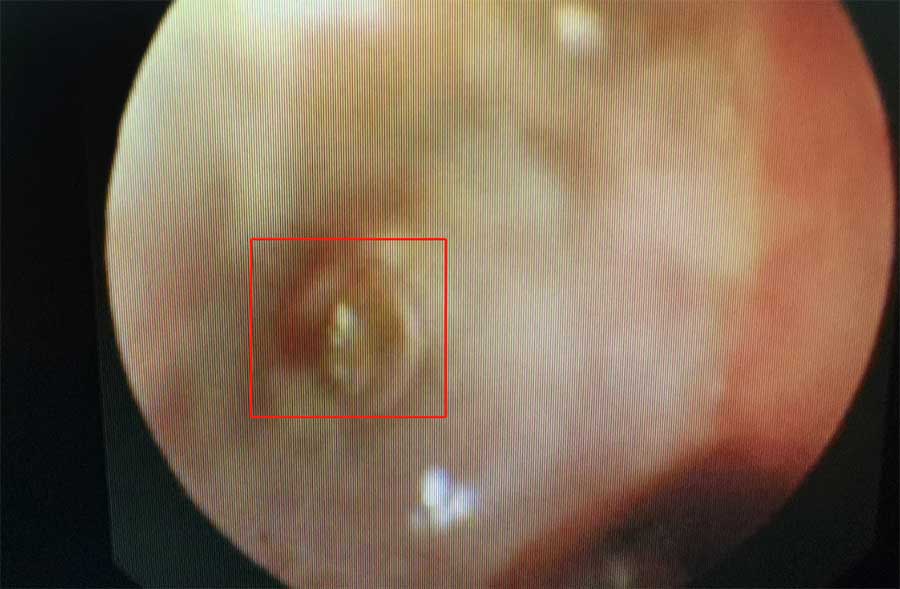

内镜中心主任赵芳兴经详细问诊,了解到:2个多月来,轩轩虽然咳得并不严重,但一直不见好,辗转了几家医院治疗,都不见效。赵芳兴再仔细追问,才发现,轩轩2个月前曾有过一次异物呛入史。是异物造成的咳嗽?支气管镜检查结果证实了赵芳兴的判断。在轩轩左肺上叶基底段有一个透明异物,周围的肉芽组织几乎将其包裹上。取出异物,是治疗的最好办法。

在内镜下,边鹏很快发现左肺上叶基底段的异物,她剥开肉芽组织,利用异物钳将异物取出。原来是一个透明的笔芯帽。除了剥开肉芽组织时有少量出血外,整个手术过程非常顺利。异物取出后,轩轩经消炎治疗,恢复良好,复查肺段通气也很好,术后第二天就出院了。